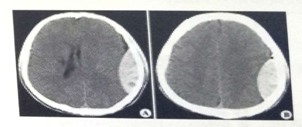

試題2:男,44歲。頭部外傷12小時。結合CT片,此診斷為(2分)

答案:C